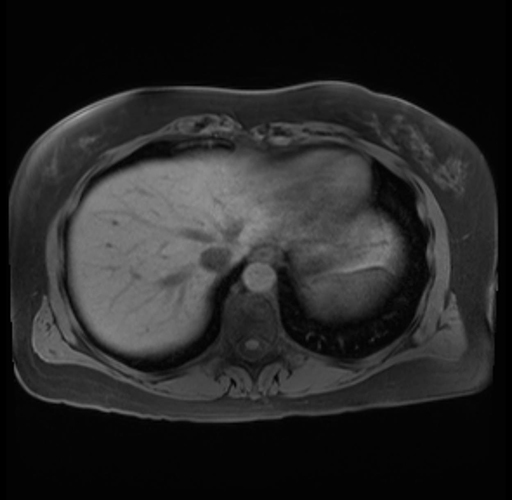

Imaging Analysis

Look through the patient's CT scan to identify any areas of concern for the necessary procedure.

Based on your CT findings, which issue(s) are present and would give reason for "planned slowing down moment(s)" in this case?